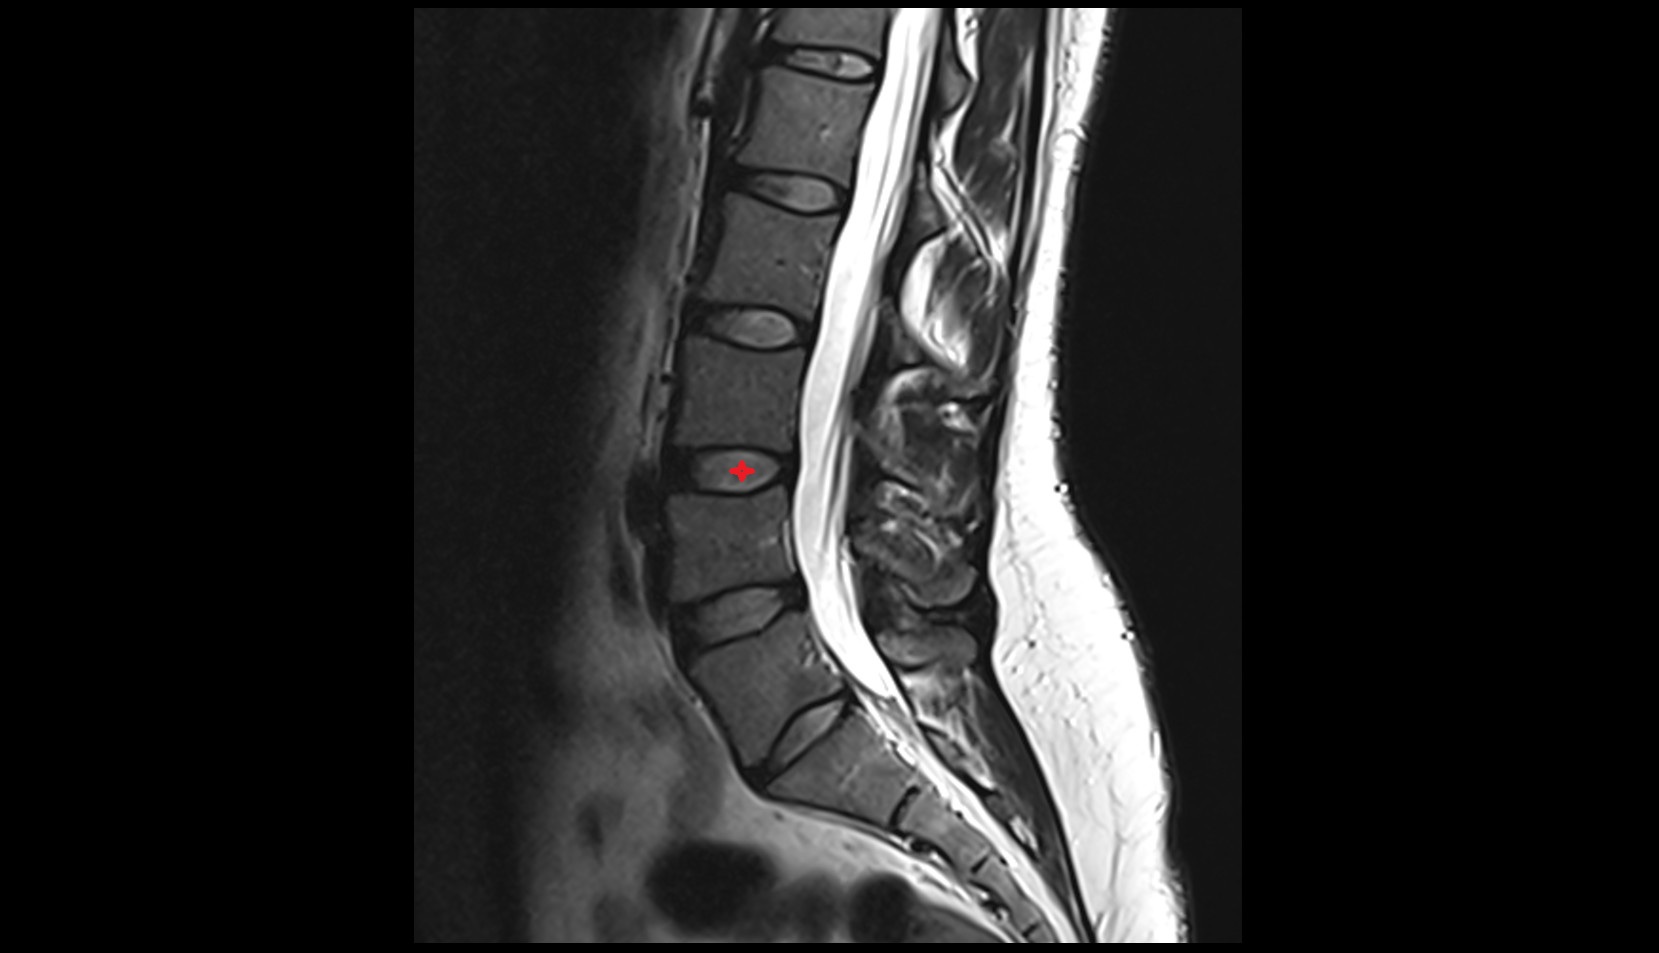

MRI image

L3–L4 Intervertebral Disc mri anatomy  image